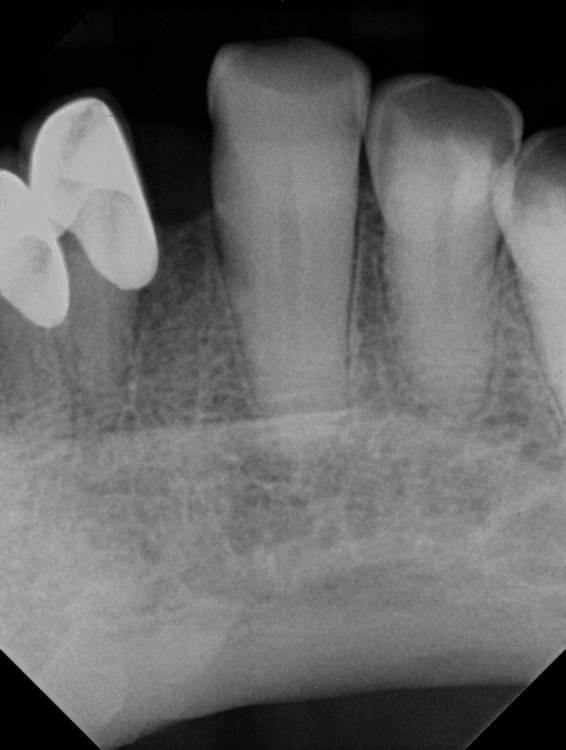

adent Опубликовано 1 апреля, 2021 Поделиться Опубликовано 1 апреля, 2021 Здравствуйте! Есть ли трудности какие либо или особенности для установки импланта (имплантата?) на место зуба №23. Мой врач имеет некоторые сомнения в успешности установки.Наращивание кости было в августе 2020 года. Возраст 79 лет. В целом здоровье мое без хронических заболеваний и аллергий. Есть ли риски какие после установки импланта через 3 дня делать длительный перелет? Спасибо! adent Ссылка на комментарий

red_butler Опубликовано 2 апреля, 2021 Поделиться Опубликовано 2 апреля, 2021 проблема как с местом для импланта (между корней ) так и для коронки 1 1 Ссылка на комментарий

kramer Опубликовано 2 апреля, 2021 Поделиться Опубликовано 2 апреля, 2021 Не влезет 1 Ссылка на комментарий

Доктор Хаус Опубликовано 3 апреля, 2021 Поделиться Опубликовано 3 апреля, 2021 Можно полу мостик сделать с опорой на зубы которые под коронкой. Ссылка на комментарий